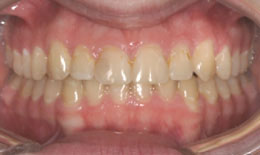

• Protruding upper arch